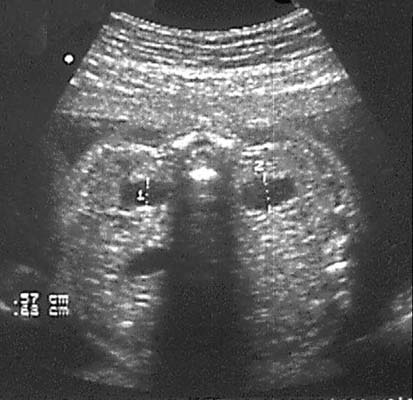

En coupe transversale : Image en « lorgnon »

Le bassinet anéchogène, à liseré très échogène avec renforcement postérieur, déborde largement en dedans du rein, en avant du rachis. Cette lacune ne doit pas dépasser 1,5 cm en transverse et 1 cm en antéro-postérieur.